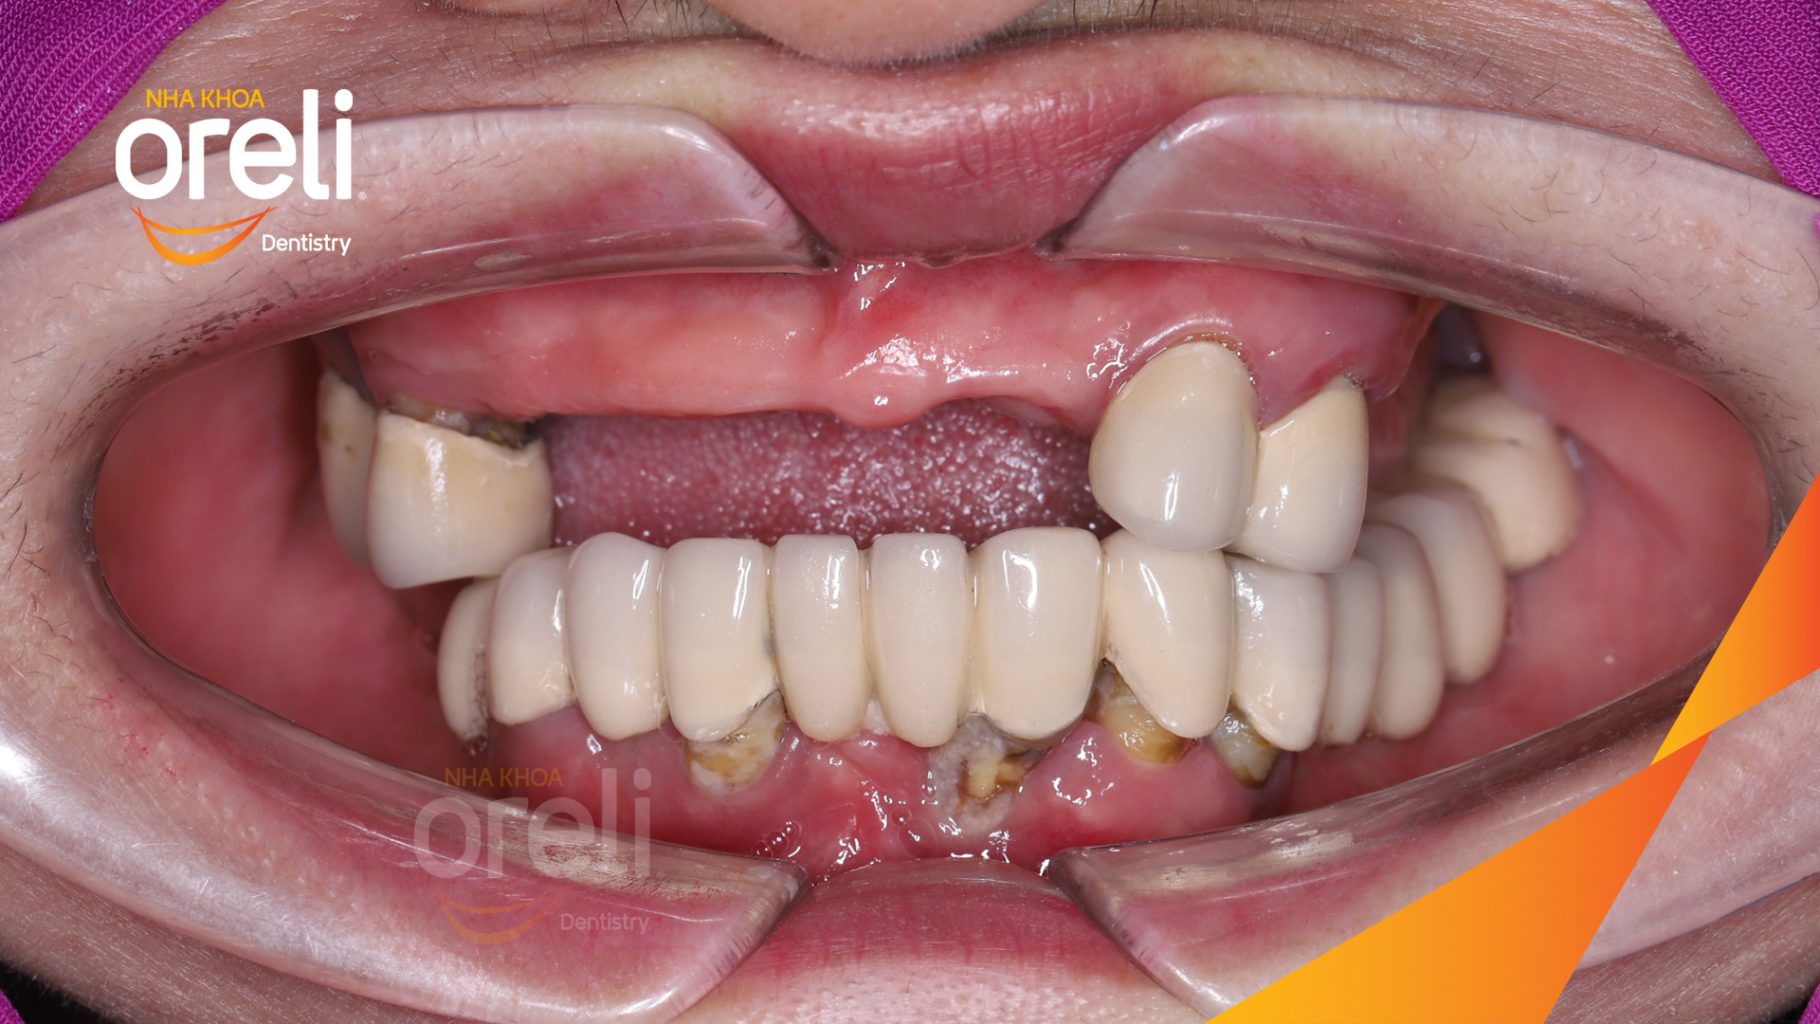

Tình trạng: Cầu răng sứ lâu ngày, tiêu xương nhiều ở cả hàm trên và dưới

Giải pháp: Cắt bỏ cầu sứ nhổ răng lung lay, cấy ghép răng implant hàm trên và dưới

Hình ảnh thực tế